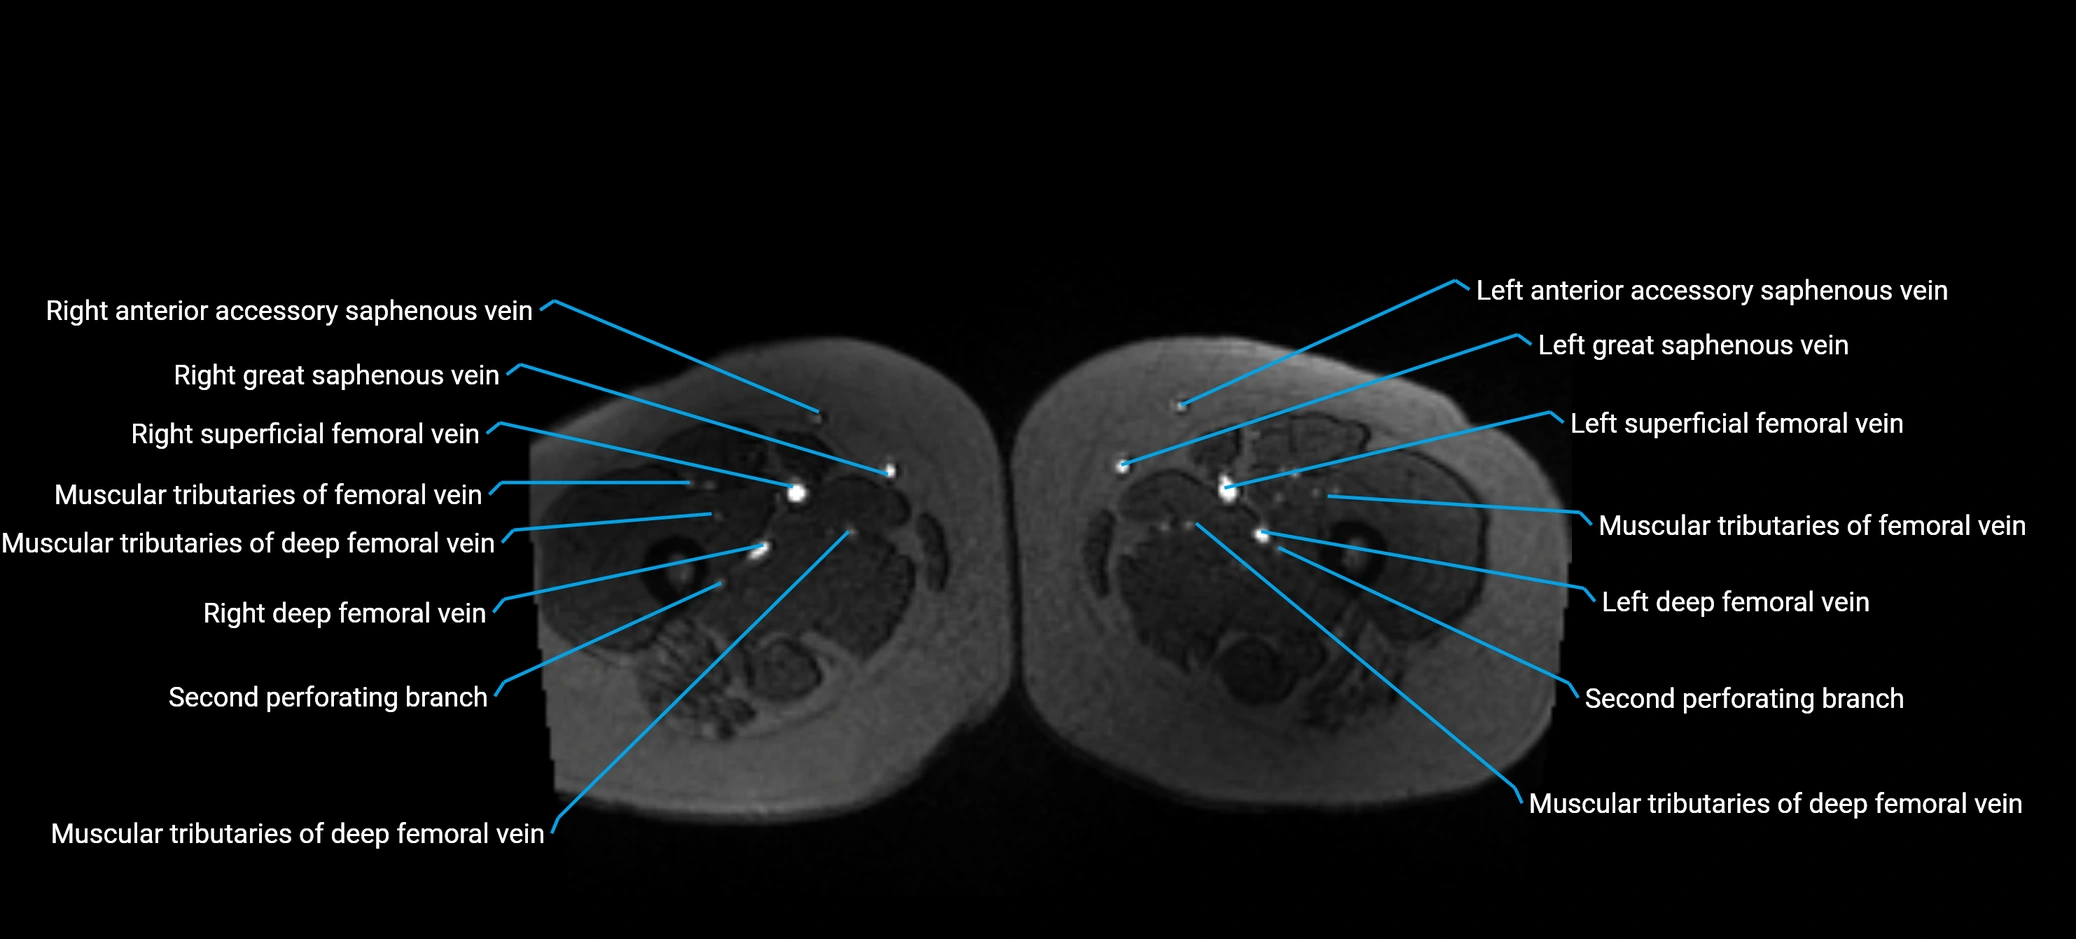

MRI image

image